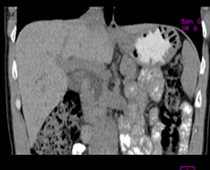

患者,男,57,常年不吃午饭,近一个月来腹部隐痛,无明显黄疸,明天进行增强扫描,图象另上传,麻烦各位帮忙一起看看讨论讨论

肝外胆管扩张,胰头增大,肠系膜上静脉似有包埋征象。

考虑:胰头占位性病变,建议增强进一步检查。

肝外胆管扩张,胰头增大,占位性病变可能性大.

肝外胆管稍扩张,胰腺钩突略增大,但外形尚可,境界清楚。(常年不吃午饭)提示胰腺炎可能大,肿瘤第二步考虑。

支持考胰头占位性病变,感觉十二指肠壁不规则增厚,不排除十二指肠降部占位可炎症

胰头增大,考虑胰头占位性病变。

胰头增大,胆总管增宽,考虑胰头癌可能性大,明天看增强片有助诊断.